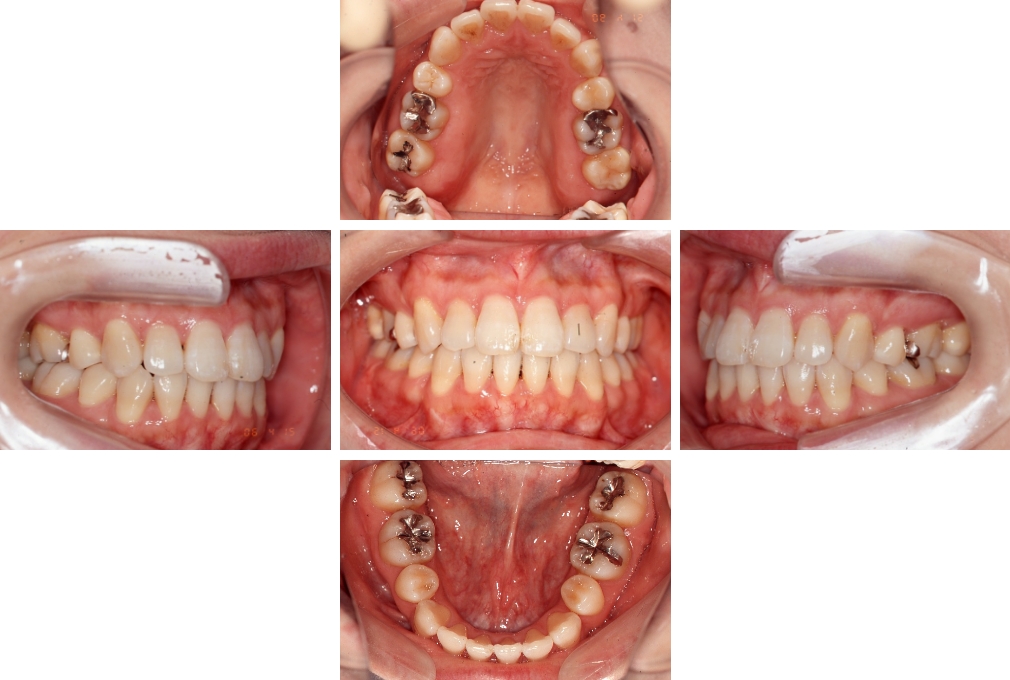

CASE:02

下顎前歯部叢生、小臼歯4歯先天欠損

初診時年齢 14歳3か月

性別 女性

治療費の目安 70万円(治療開始時)

上顎左右側小臼歯3歯、下顎左側第二小臼歯の先天欠損と下顎前歯の叢生を主訴として近隣一般歯科から紹介来院した。

上顎左側第一、第二小臼歯、右側第一小臼歯、下顎左側第二小臼歯が先天欠損であったが、左上第二乳臼歯の根の吸収がほぼ無いことから、これを残すこととして、下顎左側乳臼歯と、右側第二小臼歯を抜歯していただきマルチブラケット装置を使用して動的治療を行った。矯正用ゴムなどの協力状態も良く2年0カ月(調整来院19回)で装置を撤去し保定へ移行した。動的治療終了13年2カ月での来院時には下顎左右側智歯が萌出していたが、垂直的に萌出していたため抜歯は行っていない。

治療前

14歳3か月

治療後

動的治療期間2年0カ月

16歳7か月

13年経過

動的治療終了後13年2カ月

30歳0か月